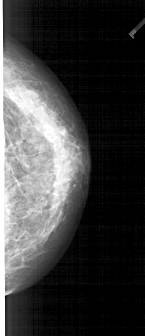

A_1938_1.LEFT_CC

LEFT_CC LINES 4651 PIXELS_PER_LINE 1951 BITS_PER_PIXEL 12 RESOLUTION 43.5 OVERLAY